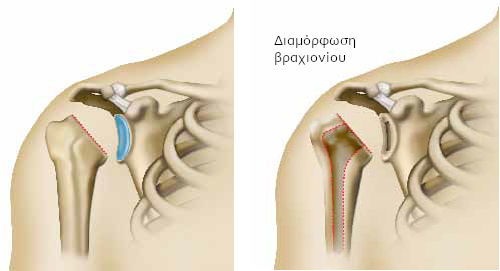

Μια περιοχή του ανώτερου τμήματος του οστού του άνω άκρου (του βραχιονίου) δεν αιματώνεται πια σωστά και νεκρώνεται. Στην ιατρική γλώσσα, μιλάμε για νέκρωση της κεφαλής του βραχιονίου (ή οστεονέκρωση).

Η περιοχή που καταστράφηκε, συνήθως, βρίσκεται κάτω από το χόνδρο. Και ο χόνδρος κινδυνεύει από φθορά.

Σε αρχικό στάδιο της ασθένειας, η εικόνα του ώμου φαίνεται φυσιολογική. Σε προχωρημένο, ωστόσο, στάδιο, παρατηρούμε παραμόρφωση της κεφαλής του βραχιονίου, που συνδέεται με τη φθορά του χόνδρου στην περιοχή που έχει καταστραφεί (νεκρωμένη).

Η βασική επέμβαση

Ο χειρουργός αφαιρεί το ανώτερο τμήμα του οστού του βραχίονα (κεφαλή βραχιονίου) και κόβει το οστό, βάσει υπολογισμών, ανάλογα με το είδος της πρόθεσης που έχει επιλεγεί. Έτσι, προσαρμόζει απόλυτα το οστό στην πρόθεση.